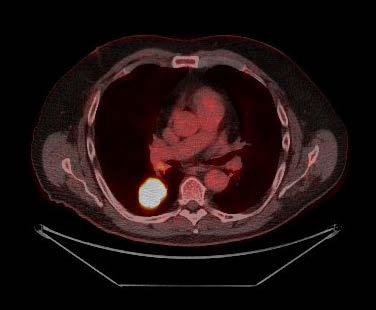

Mynd 6-1 Lítið lungnakrabbamein í hægra lunga (ör) sem fannst við skimun með tölvusneiðmyndum.

Með tilkomu tölvusneiðmyndatækni (TS) varð unnt að finna mun smærri hnúta í lungum en áður var mögulegt með hefðbundnum röntgenmyndum (mynd 6-1). Á síðustu áratugum hefur verið efnt til stórra framvirkra samstarfsverkefna, bæði í Bandaríkjunum og Evrópu. Fyrstu rannsóknir á skimun með TS voru gerðar í Japan og fyrsta alþjóðlega rannsóknin benti til þess að unnt væri að finna um